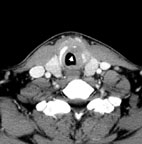

其它特定的檢查如聲帶麻痺如評估是否有甲狀腺腫瘤,或食道有無異常;聲帶的活動情形; 聲門下腫瘤(圖12~13),也可借由超音波導引下細針穿刺細胞學檢查(圖14)來診斷。另外頭頸部癌病人的頸部腫塊追蹤,頭頸部軟組織超音波也提供一個便宜又方便的方法。

圖12. 病患高先生因聲音嘶啞就診,發現左聲帶下方有腫瘤(箭頭所指處),腫瘤將環狀軟骨破壞,懷移是惡性腫瘤

圖13頭頸部超音波檢查發現有界限不明的腫瘤將環狀軟骨破壞,超音波導引下細針穿刺 (箭頭所指處) 取得細胞做檢查